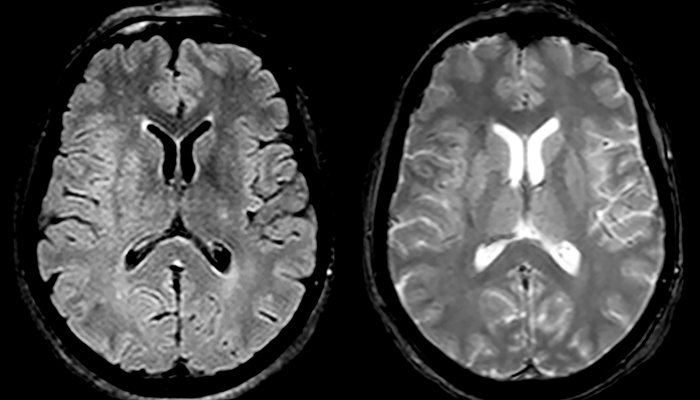

For MS imaging in the brain, Dr. Savatovsky uses 3D FLAIR as the basic sequence to visualize the lesions and assess the situation and lesion load. “We count the lesions in each location to determine if the criteria of the disease are fulfilled. We use a T2-weighted sequence because our neurologists are used to it. We compare the lesion load on FLAIR with a 3D T1 post-contrast sequence to help us determine whether lesions are old or new. We typically administer the contrast before the patient enters the machine because it shortens the examination time and allows to visualize active lesions that tend to be more visible after several minutes. When a differential diagnosis is difficult, we add sequences such as susceptibility imaging, because some focal MS lesions have a small vein in the center[3].”